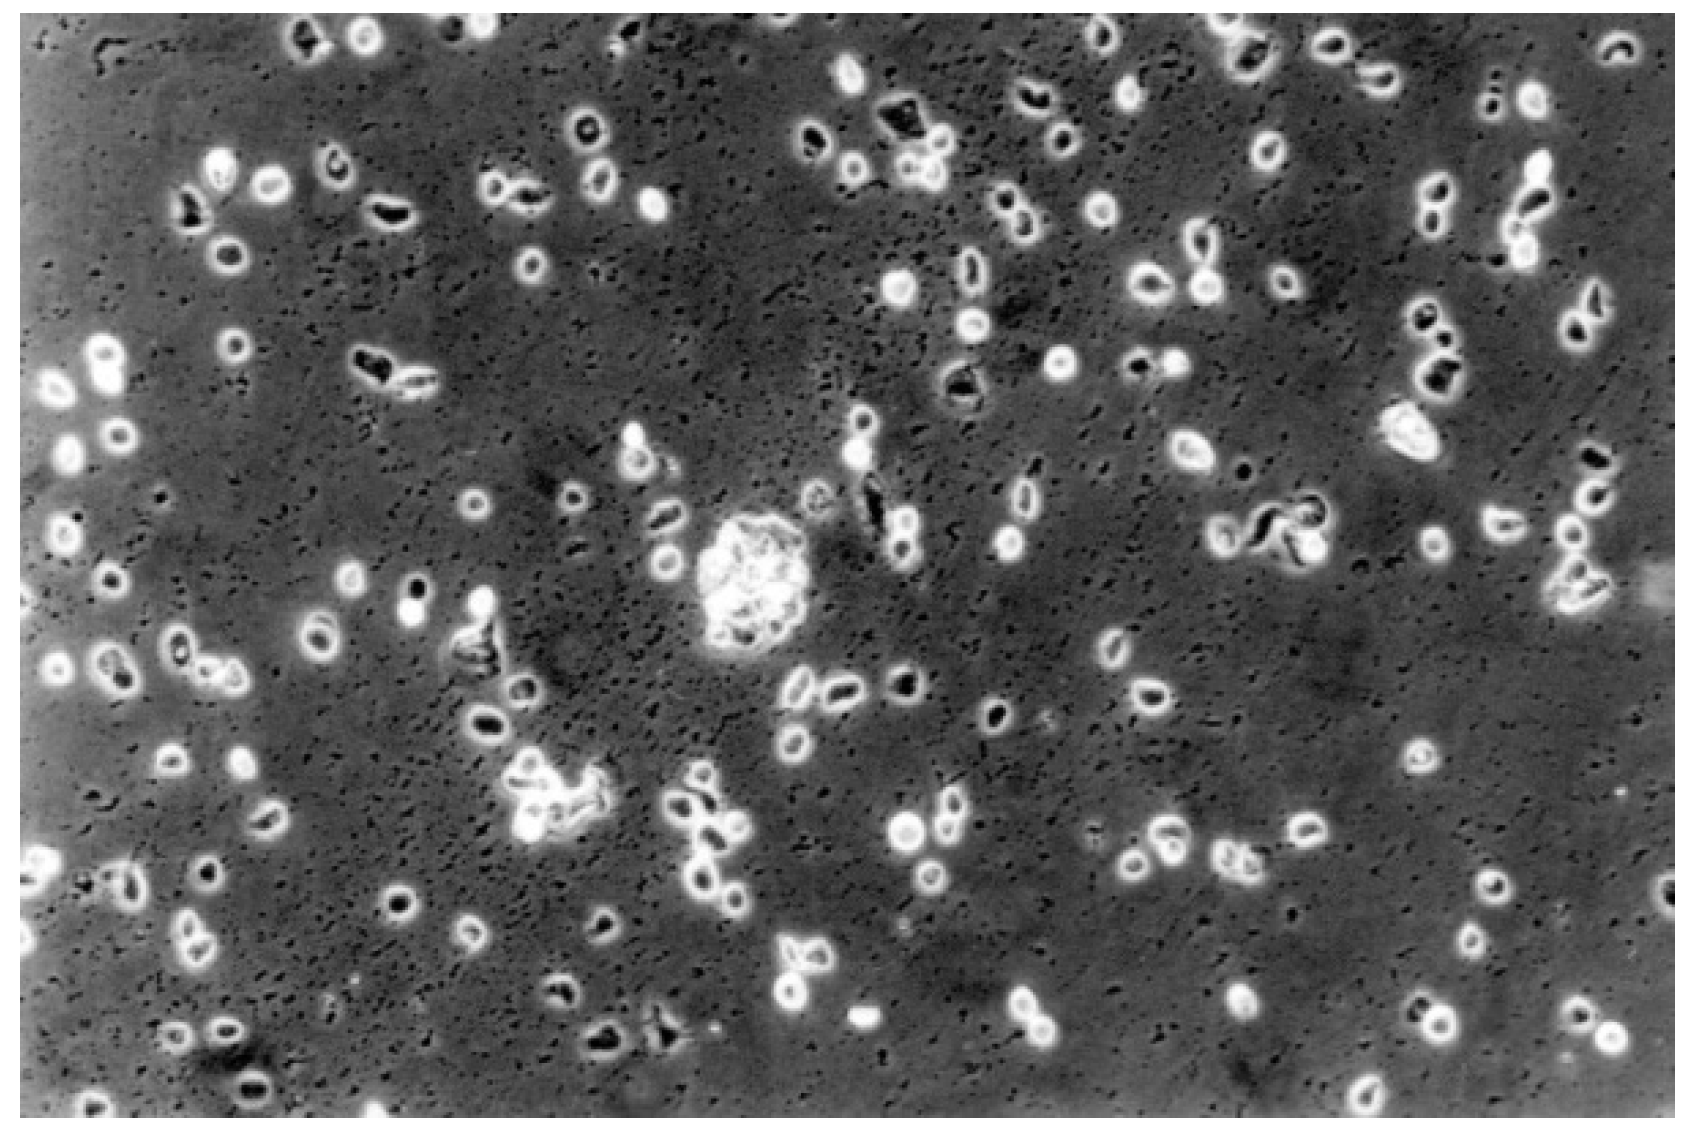

The qualitative evaluation is shown in Table 4, Table 5, Table 6, Table 7, Table 8 and Table 9. Figure 7, Figure 8, Figure 9, Figure 10 and Figure 11 showed the characteristic appearance of the cell cultures in the influence of the different dentin materials. The phenotype of this cell line has a characteristic morphology, which was observed with the use of light microscopy. This is characterized by spindle-shaped, long human primary fibroblast cells (pMF) derived from the gingiva human gingival primary fibroblast cells (HGPFC).

The contact cells to the material One-up Bond F Plus (No. 2) are rounded or dead. The fibroblast lawn is less dense than control cultures (100-fold magnification).

Figure 10.